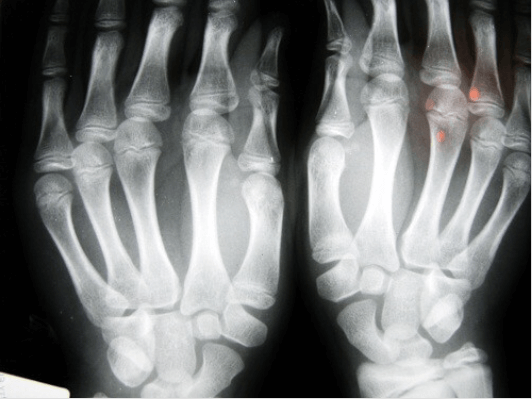

Μια από τις πιο γνωστές μελέτες πάνω σε αυτό το θέμα, ολοκλήρωσε ο Δρ. Donald Unger ο οποίος για περισσότερο από 60 χρόνια “έσπαγε” τις αρθρώσεις των δαχτύλων του αριστερού του χεριού δυο φορές την ημέρα αλλά δεν έκανε το ίδιο και στο δεξί του χέρι. Κάθε χρόνο εξέταζε τα χέρια του και ποτέ δεν βρήκε ίχνη κάποιας εκφυλιστικής νόσου ακόμη και στο χέρι που “έσπαγε” τα δάχτυλά του.

Σε μια άλλη μελέτη εξετάστηκαν 30 ηλικιωμένοι άνθρωποι σε έναν οίκο ευγηρίας στο Los Angeles. Εκείνοι που έσπαγαν τα δάχτυλά τους σχεδόν όλη τους της ζωή δεν είχαν οστεοαρθρίτιδα. Σε μια τρίτη μελέτη όπου εξετάστηκαν ενήλικες ηλικίας 45 ετών στο Ντιτρόιτ, ανακαλύφθηκε ότι το βασικό πρόβλημα που αντιμετώπιζαν ήταν η μειωμένη δύναμη της λαβής και πάνω από το 80% αυτών υπέφεραν από πρήξιμο στα χέρια τους.